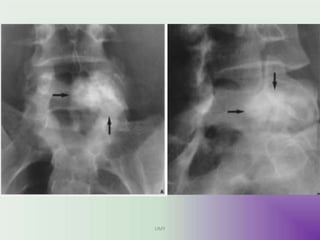

Radiographic features

• X ray

sharply defined, expansile

osteolytic lesions, with thin

sclerotic margins.

Eccentricity is typical.

But very often missed out due to

cortical thinning due to ballooning.

CT

Demonstrates these findings to a

greater degree, and is also better at

assessing cortical breach and

extension into soft tissues.

Fluid fluid levels (better than MRI)

• MRI

Demonstrate Fluid Fluid level in lesion.

To distinguish between Primary and secondary (if

solid component Is present.)

The cysts are of variable signal, with surrounding

rim of low T1 and T2 signal. Focal areas of high T1

and T2 signal are also seen presumably

representing areas of blood of variable age.

SBC vs ABC on MRI- Presence of double density

fluid level & intralesional septations- ABC